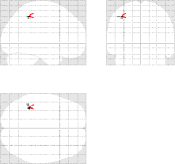

Fig. 10 illustrates another property of the proposed pMRI pipeline, i.e. its robustness to the between-subject variability. Indeed, when comparing subject-level Student’s -maps reconstructed using the different pipelines (), it can be observed that the mSENSE algorithm fails to detect any activation cluster in the expected regions for the second subject (see Fig. 10 [bottom]). By contrast, our 4D-UWR-SENSE method retrieves more coherent activity while not exactly at the same position as for the first subject.

| mSENSE | UWR-SENSE | 4D-UWR-SENSE | |

|---|---|---|---|

| Subj. 1 |  |

|

|

| Subj. 2 |  |

|

|